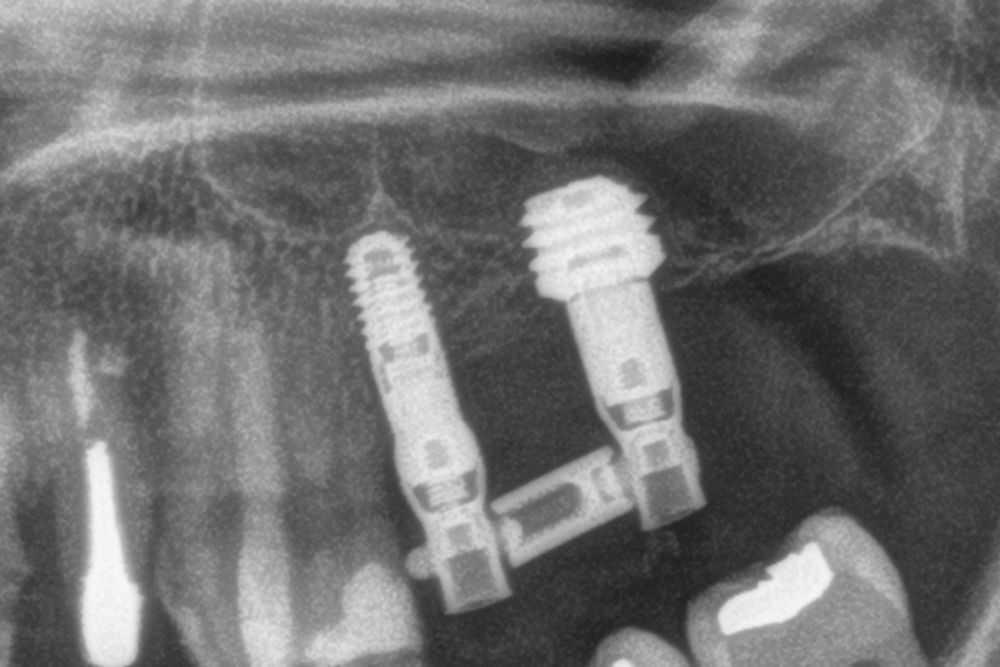

Entre cuatro y cinco meses meses después se realiza la carga del implante, en una primera fase con una prótesis provisional de carga progresiva, siempre mediante transepiteliales y, posteriormente la prótesis definitiva entre 1 y 2 meses tras la carga inicial.

Para estimar la pérdida ósea marginal, se utilizó una referencia de longitud conocida en las radiografías, específicamente la longitud del implante, con el fin de calibrar las mediciones obtenidas. A partir de esta calibración, el software empleado (Digora for Windows, SOREDEX Digital Imaging Systems) calculó las mediciones reales. La pérdida ósea crestal marginal se determinó midiendo la distancia desde el hombro del implante hasta el primer punto donde se evidenció contacto óseo con el implante. Para evaluar la evolución de la reabsorción ósea en cada paciente, se utilizó como referencia la radiografía tomada en el momento de la colocación de la prótesis. Posteriormente, los pacientes asistieron a controles periódicos cada seis meses, en los cuales se realizaron nuevas radiografías de seguimiento. Durante las visitas postoperatorias y tras la colocación de la prótesis, se registraron en la historia clínica cualquier posible complicación protésica o quirúrgica, las cuales fueron posteriormente analizadas.

La media de seguimiento de los implantes estudiados fue de 36,3 meses (+/- 2,71); rango 36-42 meses y durante este tiempo no se produjo ningún fracaso, siendo la supervivencia acumulada del 100%. La media de la pérdida ósea mesial al final del seguimiento para todos los implantes fue de 0,35 mm (+/- 0,62) mientras que la distal fue de 0,11 mm (/- 0,49).

En las Figuras 7- 13 se muestra uno de los casos incluidos en el estudio.